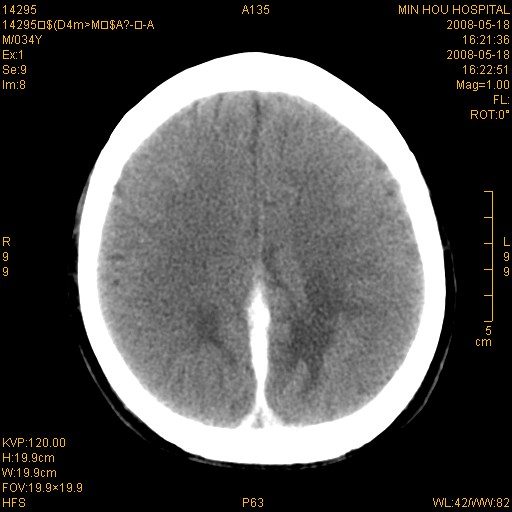

标题: CT13617:双顶叶白质水肿伴大脑镰小脑幕广泛钙化 [打印本页]

标题: CT13617:双顶叶白质水肿伴大脑镰小脑幕广泛钙化

多年前频发抽搐生活不能自理,行ct平扫,诊断为双顶叶占位。因贫未能进一步检查。

目前偶有抽搐,能从事油漆工作。原片未能获取。

双侧侧脑室后脚旁对称性低密度影,符合肾上腺白质营养不良(成人型)改变    小脑幕及大脑廉钙化  可考虑为生理性

支持:1、肾上腺白质营养不良.2、小脑幕、大脑镰广泛钙化。3、建议进一步检查。

硬脑膜钙化是主因,双侧顶叶白质密度减低是可能由于静脉路回流受阻所致。